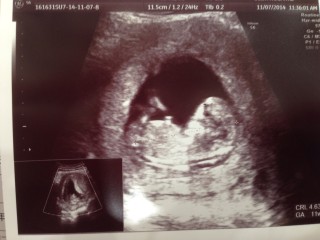

3週間ぶりの検診!47.5mmでした!前回は16.5mmだったので大きくなっているのに感動しました。そして今回から初めての腹部エコーでした。どんどん人間らしくなって愛おし差が増します。

2週間で一気に人間になっていて感動しました!こっち向いてて可愛い♪

CRL 41.0mm

手を握ったり開いたり

力強くキックしたりしてました!

ちょうど右足をキックしたところですね!